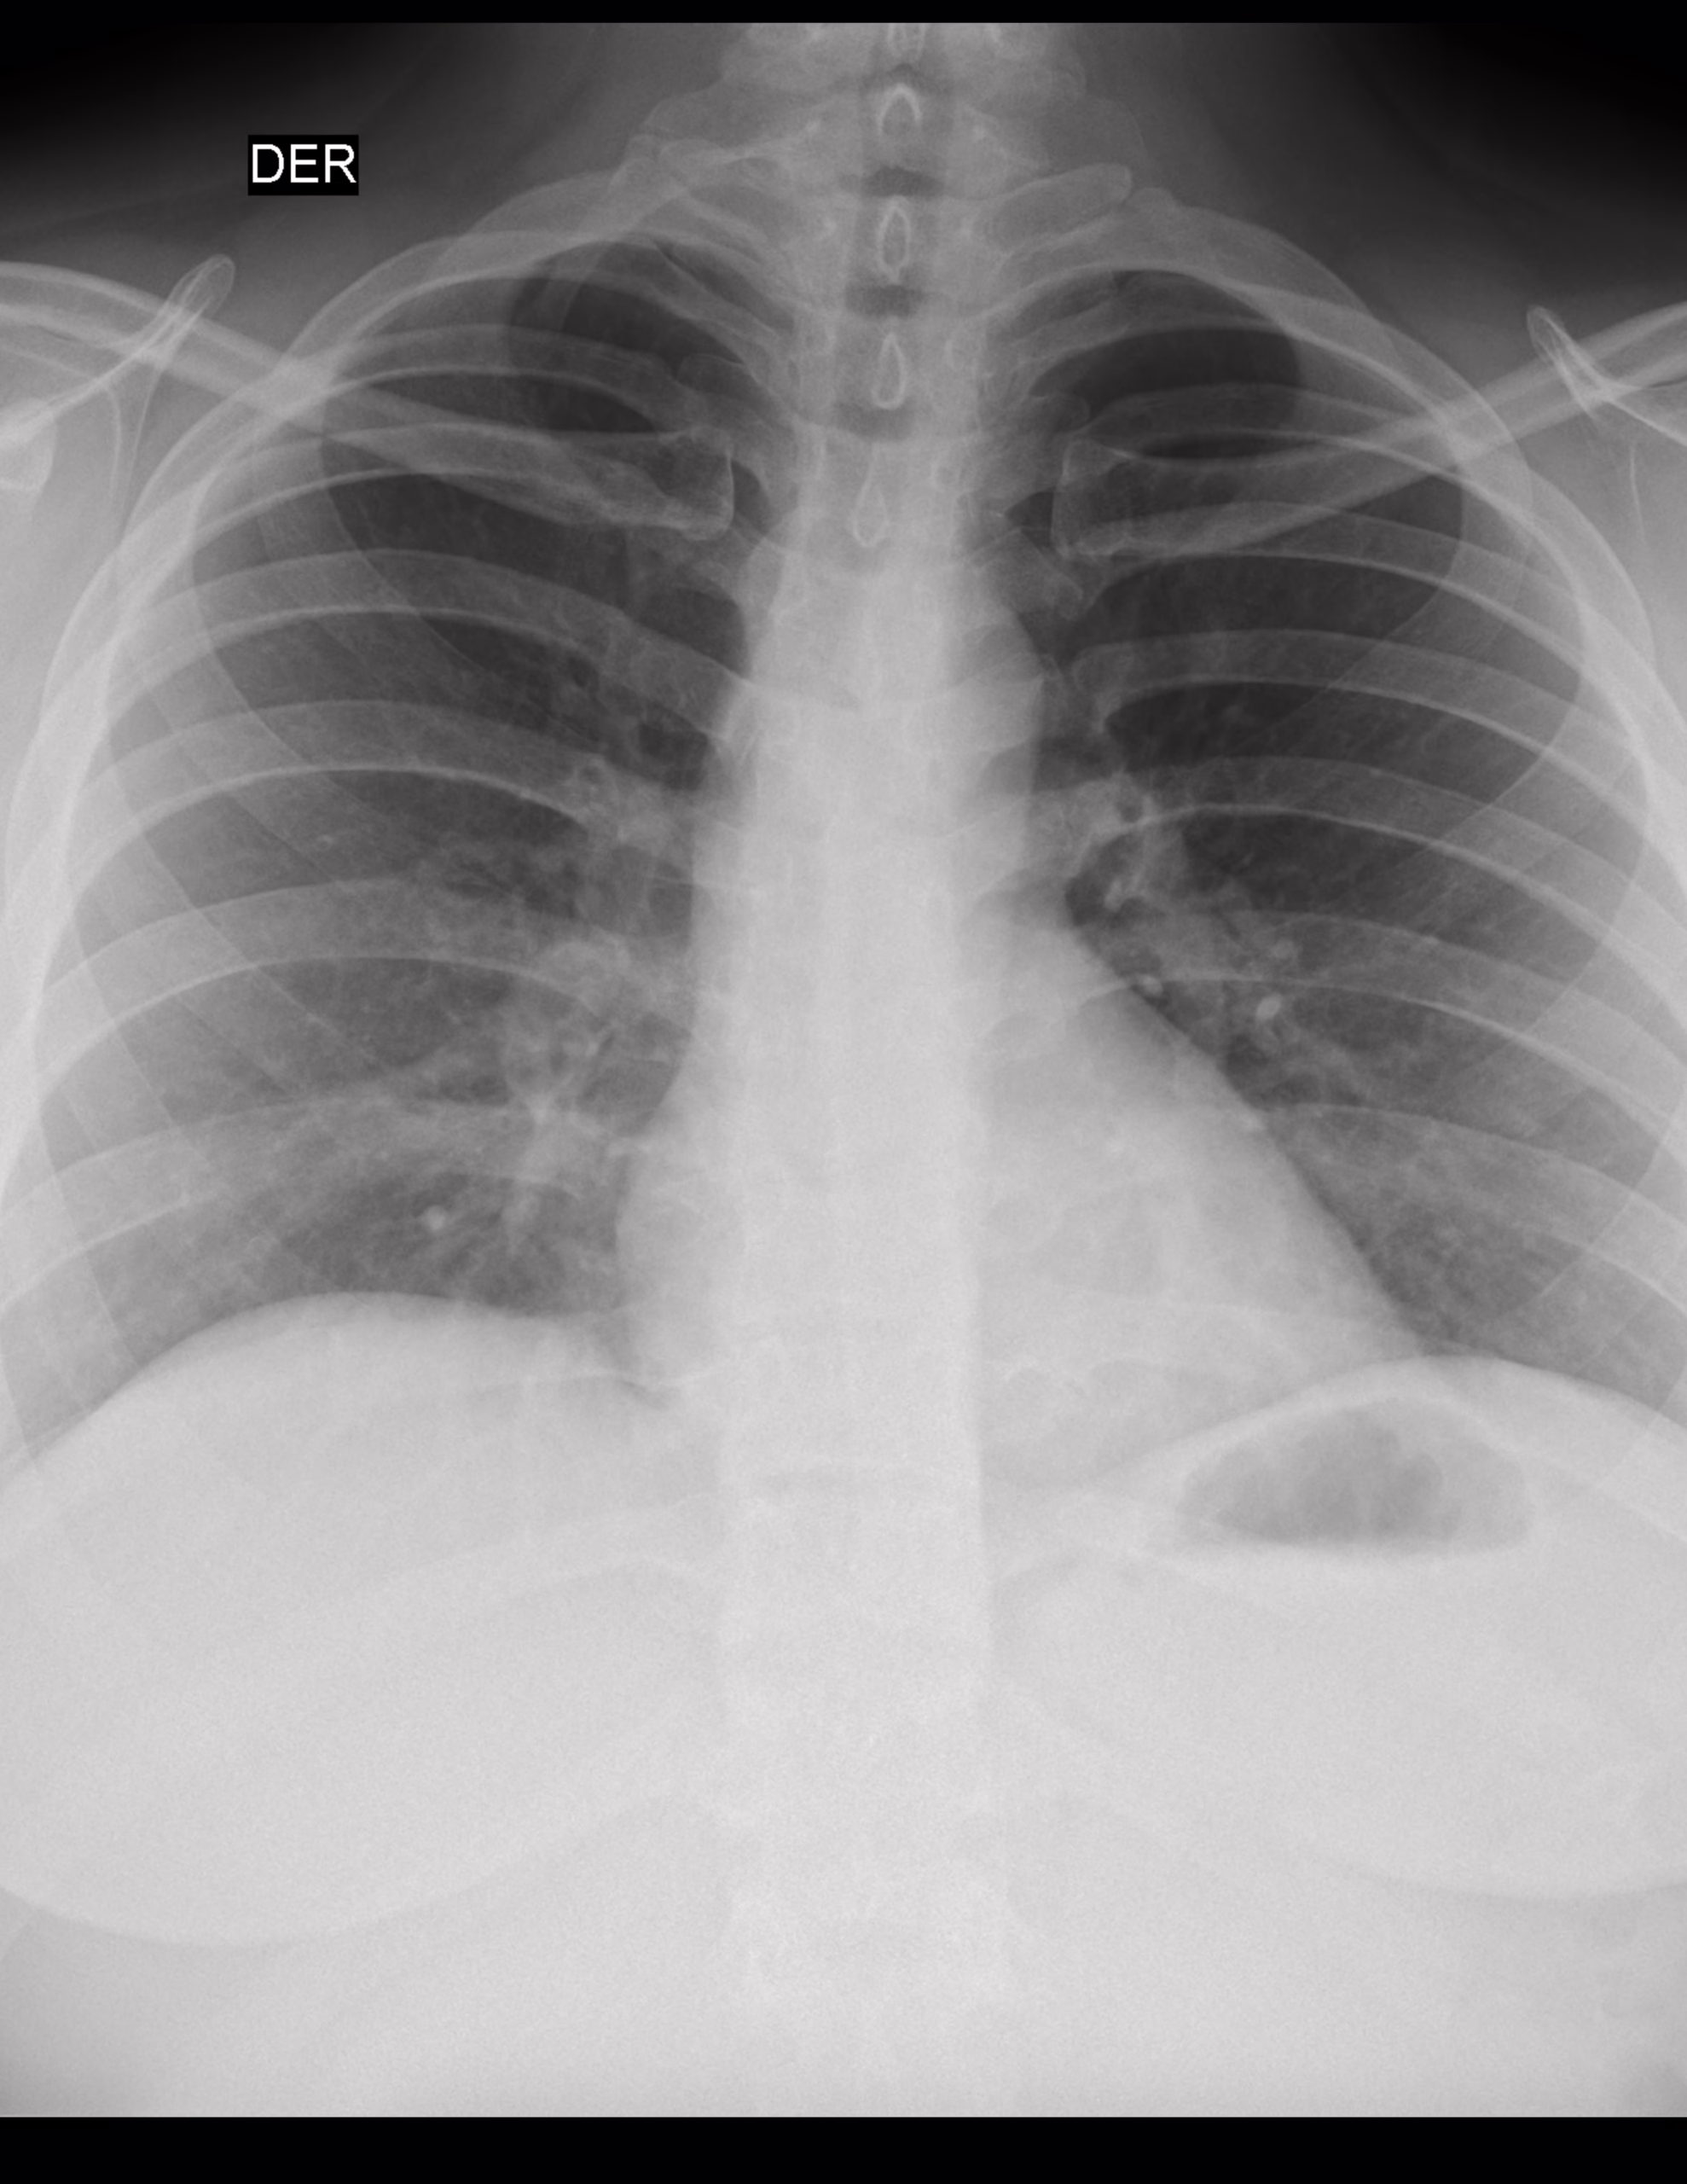

LA PROYECCION RADIOLOGICA OBTENIDA NOS MUESTRA LOS SIGUIENTES HALLAZGOS:

-Tejidos blandos son simétricos, con adecuada densidad y grosor.

-Estructuras óseas, sin evidencia de lesiones líticas, blásticas o perdida de la contigüidad.

-Vía aérea permeable, central. Botón aórtico sin calcificaciones.

-Mediastino, conservando sus diámetros.

-Corazón, central, con índice cardiotorácico menor de 0.5

-Hilios pulmonares, sin alteraciones.

-Trama bronco-vascular, con adecuado trayecto, con adecuada densidad.

-Campos pulmonares, hacia parénquima pulmonar derecho, a nivel basal con presencia de imagen ovoidea, homogéneas, radiopacas, regular, bien definida, que mide 4.2 X 3.7 mm. Parénquima pulmonar izquierdo, hacia área para hiliar en segmentos inferiores, con presencia de imágenes, ovoidea, homogéneas, radiopacas, regulares, bien definidas, que miden 3.3 X5 mm, 2.9 X 5.2 mm, 5.6 X 3.4 mm.

-Recesos costofrénicos y cardiofrénicos se observan libres.

OPINIÓN RADIOLÓGICA:

EN EL PRESENTE ESTUDIO RADIOGRÁFICO, SIN EVIDENCIA DE LESIONES PARENQUIMATOSAS.

HACIA NIVEL BASAL DE PULMÓN DERECHO Y PARA HILIAR INFERIOR DE PULMÓN IZQUIERDO CON IMÁGENES SUGERENTES DE MICRONÓDULOS VS GANGLIOS DE CARACTERÍSTICAS BENIGNAS.

LEER DESCRIPCIÓN Y OTORGAR VALOR DIAGNÓSTICO.

CORRELACIONAR CON DATOS E HISTORIA CLINICA DEL PACIENTE